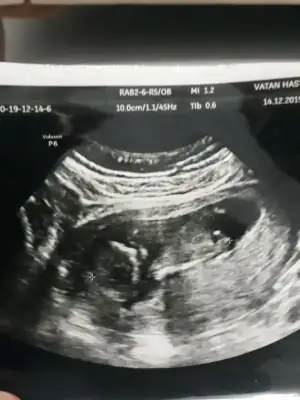

Kız gibi gibi sanki eminde değilim başka usg varmıArkadaşlar 13 haftalık yorumlarınızı bekliyorum çatladımmmmm![]()

Evet var onuda atatum hemenKız gibi gibi sanki eminde değilim başka usg varmı

Yok cnm net degil bu usg daha pusluEvet var onuda atatum hemen![]()

Şekil almamış kız olabilirkizlar buna da yorum yapar misiniz. 10

hafta icinde

şekil almamış derken. kötü birşey miŞekil almamış kız olabilir

Hayır ne den kötü olsun erkek bebekleri de uzuvlar daha net belli oluyo bu haftalarda o yüzden dedim kız olabilir diyeşekil almamış derken. kötü birşey mi

Bilmiyordum ondan sordum teşekkür ederim.Hayır ne den kötü olsun erkek bebekleri de uzuvlar daha net belli oluyo bu haftalarda o yüzden dedim kız olabilir diye